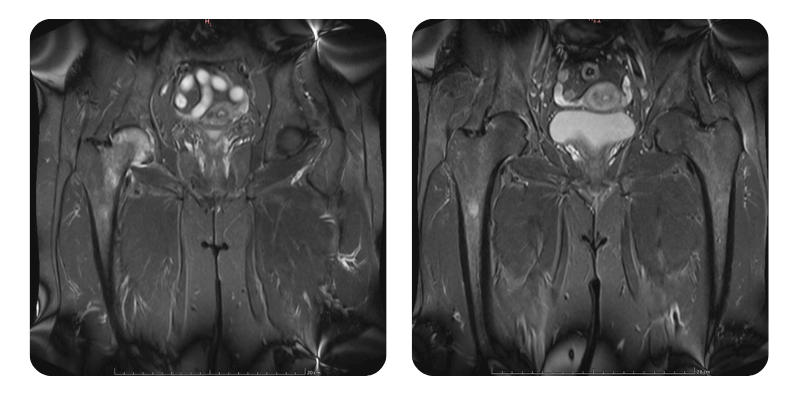

Prima

Dopo

C.L.A., 56 anni - Necrosi asettica della testa del femore destro, stadio 2

Anamnesi: Paziente di 56 anni con necrosi asettica della testa femorale destra, stadio 2, che si presenta in clinica con dolore 7/10 alla regione dell'anca, lombare e sacrale, insorto da circa 3 settimane e accentuato negli ultimi giorni. Durante questo periodo ha assunto antinfiammatori non steroidei e desametasone, seguiti da ulteriori indagini diagnostiche.

Diagnosi: Necrosi asettica della testa femorale destra, stadio 2. Discopatia lombare. Coxartrosi destra. Sinusite cronica.

Evoluzione: Dopo il secondo ciclo di trattamento, la paziente riferisce scomparsa del dolore e sospensione completa della terapia farmacologica. Anche sinusite e cefalea sono regredite.